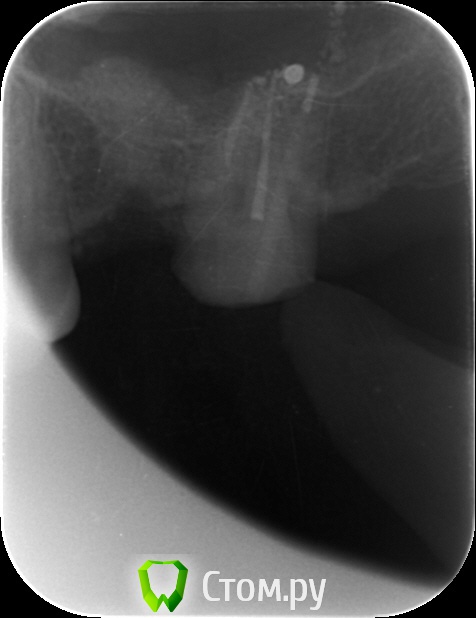

4ebstom Опубликовано 29 мая, 2014 Поделиться Опубликовано 29 мая, 2014 Имплант недокручен или снимок такой? Ссылка на комментарий

an_ver Опубликовано 29 мая, 2014 Автор Поделиться Опубликовано 29 мая, 2014 Имплант недокручен или снимок такой?Наверно снимок косой)) Счас с формиком ходит.Поставлю коронку отфотаюсь))) Ссылка на комментарий

an_ver Опубликовано 30 мая, 2014 Автор Поделиться Опубликовано 30 мая, 2014 1. Сколько в итоге подняли?2. Имплант какой длины?3. У Вас Rg в кабинете стоит?1. 4 мм 2.3,75*10 мм SPI 3.Rg да,в каждом своя пушка...дорого но удобно..RVG без проводов Дигора Ссылка на комментарий